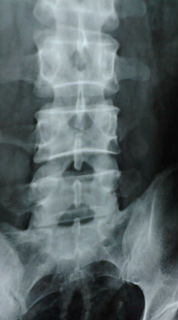

朝九時に造影剤のレントゲン撮影のため、病院に入る。

二日酔いの中(笑)、淡々とレントゲンが終わり、ドクターのいる診療室に向かう。

いつもならレントゲン室と診療室までの廊下で、レントゲンを盗み見る。

うぬぬ〜、まだ石が大きいままだ...、などと考えながら移動するのだ。

今日は二日酔い、けだるい空気が漂って、盗み見するのも忘れていた。

診療室に入るとドクターが「あれ?!、石がなくなってるね!」

慌ててレントゲンに目を移すと、確かにない!、なくなってる〜っ!

下に降りてきていて、おそらく勝手に排出されるだろうとのことだった。

真ん中の白い2つの結石 なくなったぁぁ!